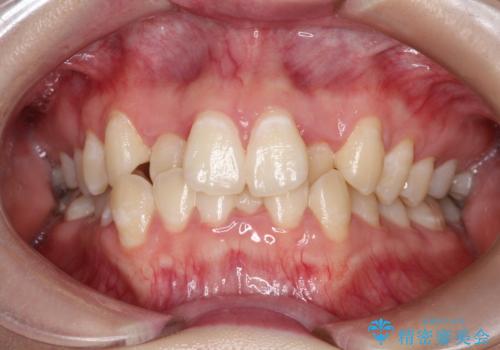

invisalign lite インビザライン ライト で軽度なガタつきの改善を

- 非抜歯・インビザラインによる軽度の叢生改善治療を計画した

14枚のマウスピースにより改善可能な軽度の叢生であれば、インビザラインのライトパッケージにより短期間・リーズナブルに改善が可能です。

ただし、作成可能なシミュレーションやアライナーの作り直しに限度があるため、そのことに関し十分な理解が必要です。